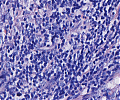

Multiples Myelom

Erkennbar sind dicht gepackte plasmazytoide Tumorzellen.